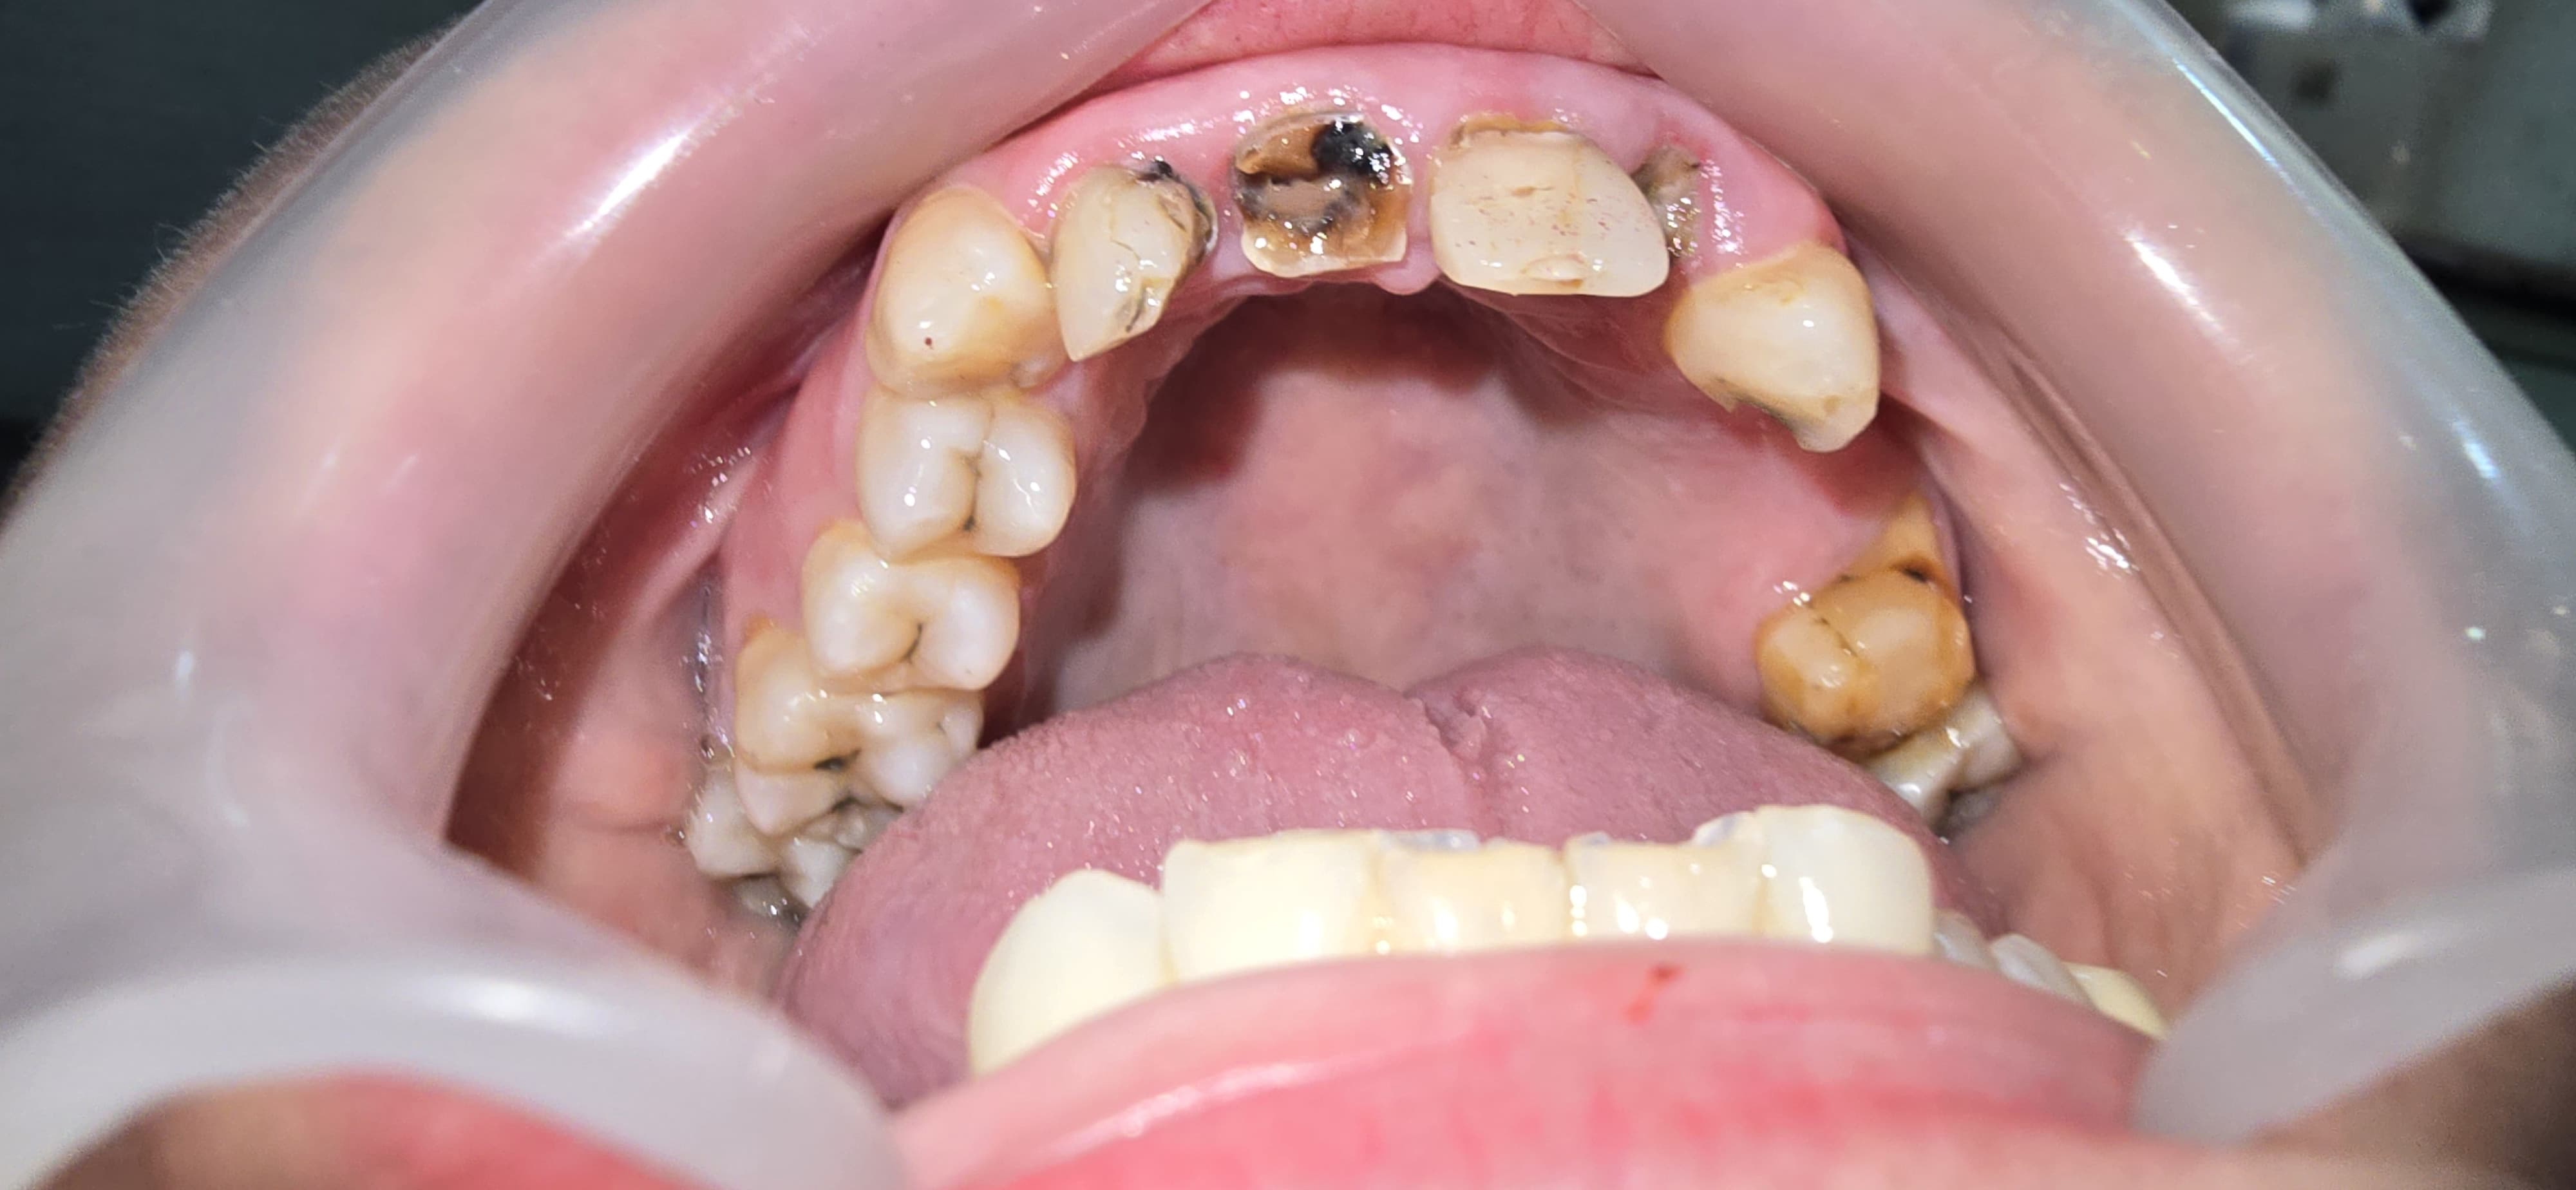

Re-Construction of broken tooth with post and core